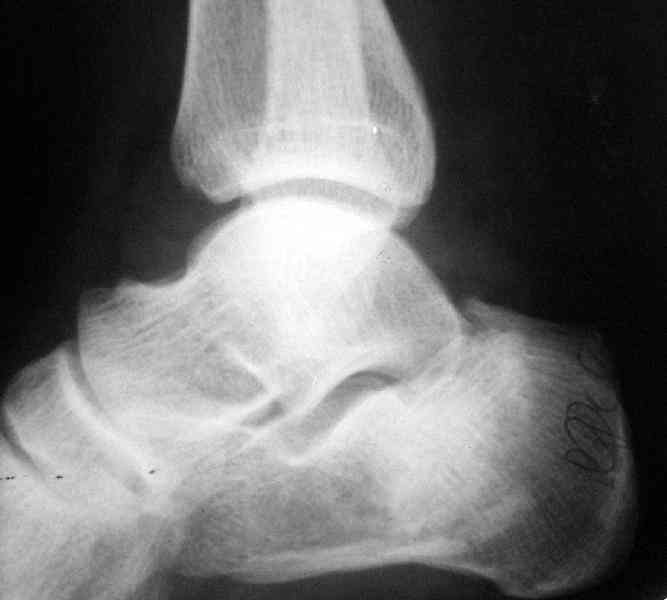

Если я правильно понял, вы хотели спросить: "Что делать с кистой, и как на этом фоне выполнять репозицию и фиксацию перелома?"

Я думаю, что для начала нужно выполнить КТ пяточной кости и определиться с границами полости. Не исключено, что отрывной перелом верхнего полюса бугра носит патологический характер (верхняя стенка кисты).

Its a comminuted one.

I would have a CT prior 2 surgery(If u have to postpone a surgery for it - I would operate without one)

Сустав похоже интактен, киста под вопросом,даже при наличии опыта остесинтеза пластиной, в данном случае выведение правильного угла и фиксация спицами более чем достаточно, да и намного спокойнее сон у хируга.

Сустав похоже интактен, киста под вопросом,

Перелом безусловно внутрисуставной. Киста-не киста принципиального значения не имеет.